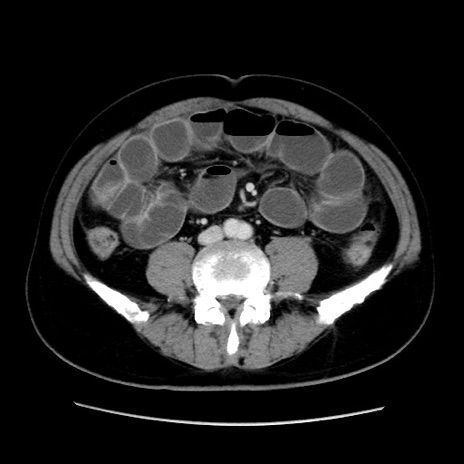

症例16(横断像)

冠状断像

【症例】 70歳代男性

【主訴】 腹痛、嘔吐

【現病歴】 約1ヶ月前より間欠的に腹痛と嘔吐あり、当院消化器内科を受診したところCTで多発する肝臓のLDAを指摘され、精査中であった。以降は消化器症状は安定していたが、2日前より嘔気と腹痛があり、同日より排便・排ガスが消失した。改善認めず、 本日、救急外来を受診した。

【既往歴】 大腸ポリープ切除後。

【身体所見】意識清明・会話良好、BT 36.3℃、BP 127/80mmHg、 P 80bpm、腹部:膨満あり、平坦・軟、上腹部正中および下腹部正中に圧痛あり、反跳痛なし、筋性防御なし。

【データ】WBC 7200、CRP 0.77